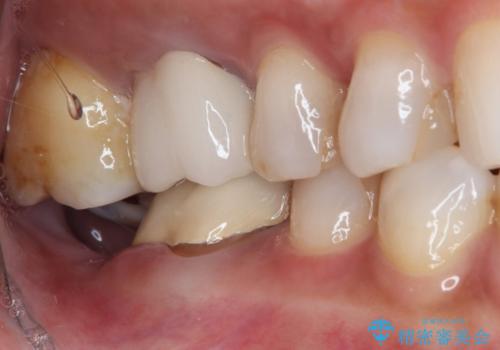

放置した奥歯 部分矯正を併用したインプラント補綴治療

- 右下欠損部のインプラント治療を希望して来院された患者様です。

右下の欠損部を長期間欠損を放置していたことで、咬み合う上の奥歯が動いてしまっていたので、まずは上顎奥歯の部分矯正を行うこととしました。

理想的な咬み合わせに改善した上で、インプラント補綴治療を行うこととしました。

部分矯正を行ったこと治療期間は長くなりましたが、違和感のない咬み合わせを達成することができました。